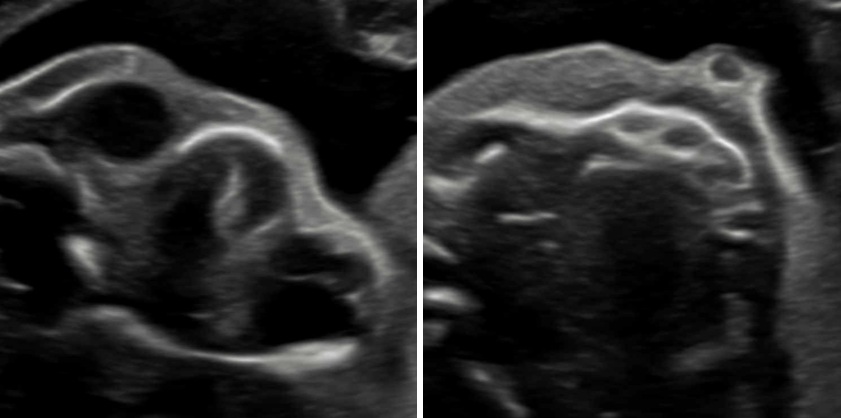

„Feindiagnostik“: 20-24 SSW

Wir schauen Ihr Kind im Ultraschall detailliert von Kopf bis Fuß an. Mit Fortschreiten der Schwangerschaft liegt der Fokus hier besonders auf der Entwicklung von Herz und Kopf Ihres Kindes. So können wir Besonderheiten frühzeitig erkennen, die Schwangerschaft optimal begleiten und die Geburt bestmöglich vorbereiten. In manchen Fällen ist eine Behandlung bereits während der Schwangerschaft möglich.